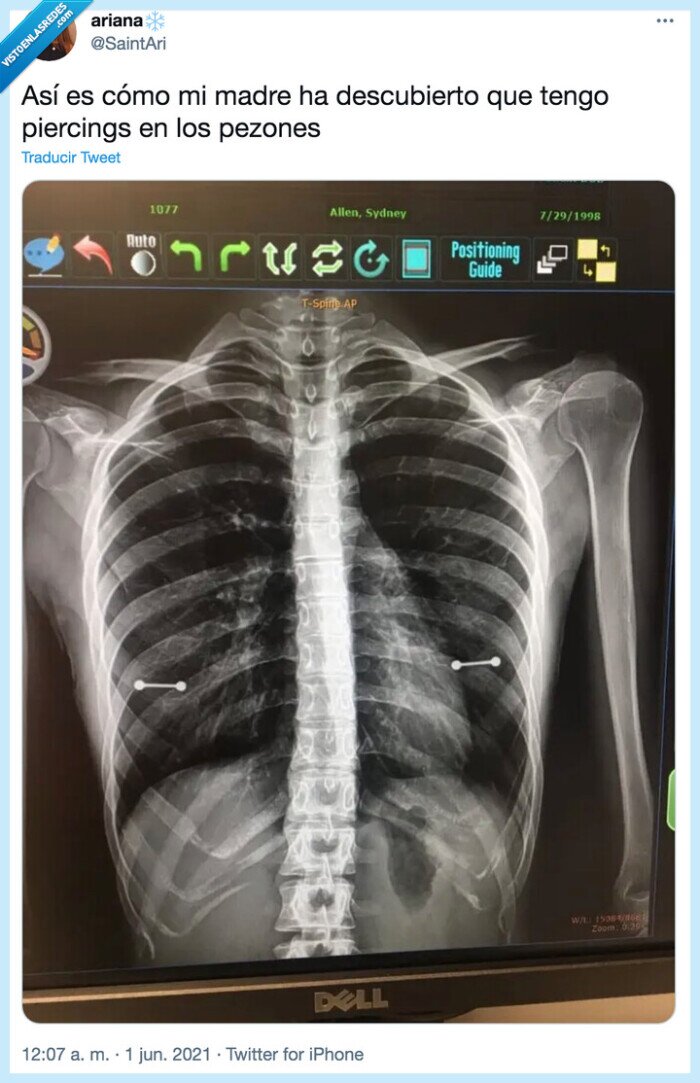

Publicado por chuckbass el 6 jun 2021, 00:30

Tarde o temprano se enteraría, por @SaintAri

radiografía,pezones,piercing

Vía: https://twitter.com/SaintAri/status/1399487643851714560